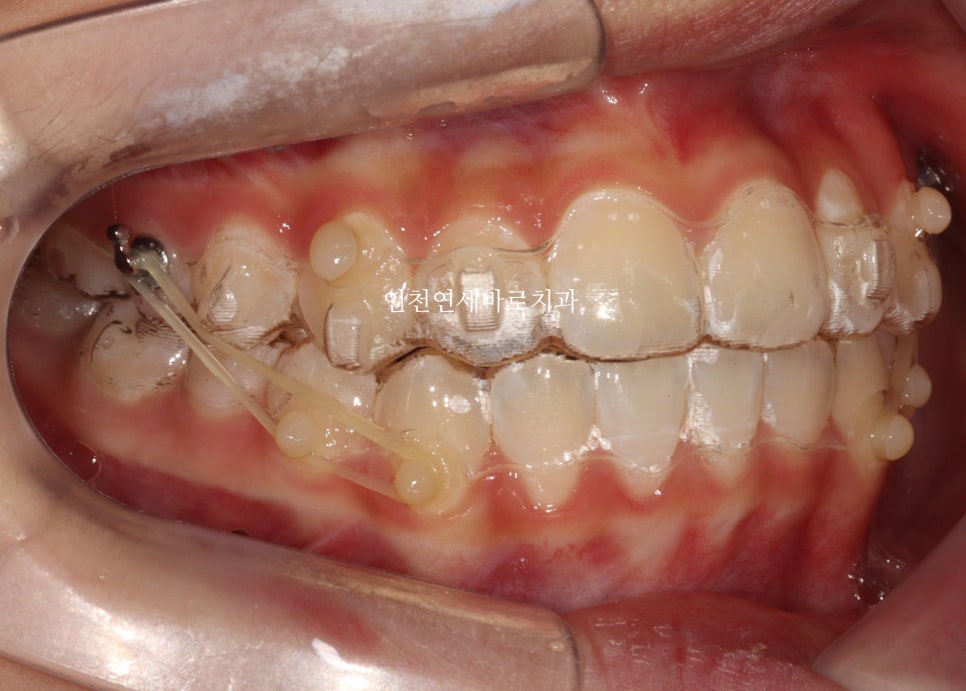

인비절라인을 하면 다양한 변수가 생깁니다.

변수마다 재제작을 하면 치료기간이 너무 길어져요.

변수에 대응하는 방법은 여러가지가 있는데 이 친구는 고무줄 사용을 했습니다

최후방 치아가 나올때 약간 삐뚤게 나옴으로 인해 1회 재제작을 했습니다.